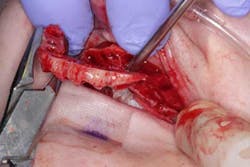

Surgery commenced. Implants on the lower arch were placed first (figures 7 and 8) and then we switched to the maxillary. The teeth were removed (figures 9 and 10) and the ridge was evened out (figures 11-13). The implants were aligned with the denture (figure 14) and then placed accordingly (figures 15-17). Healing caps were put on, and we were ready to start the restorative phase (figures 18-19).

The maxillary arch was indexed first as there was support from the palate to reference position (anterior/posterior) (figure 20). Then the lower was put into position to gain proper vertical dimension and occlusion. It, too, was then indexed; both upper and lower were given to the lab technician to start the conversion process. Next, impression copings were placed (one arch at a time) and secured with paperclips; a full-arch PVS impression was taken and likewise sent to the lab (figures 21-23). Finally, after the conversion process was completed, the bridges were secured in place on the multiunit abutments, torqued to 15nCm, and covered. Bite was adjusted and follow-up care was arranged (figures 24-26).